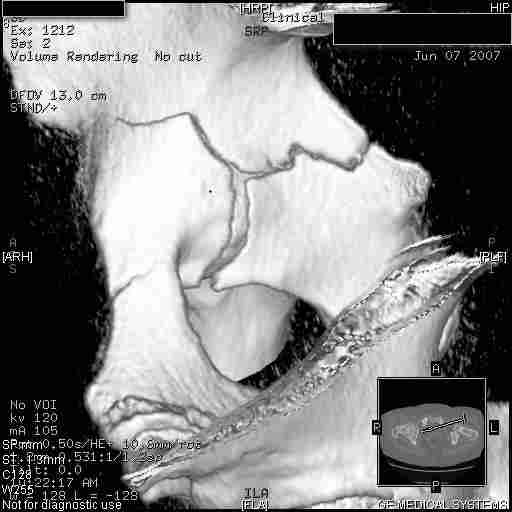

Следом 3d

Приветствую,Антон.Рункова рядом нет,но после полученных данных КТ,обсуждали совместно.Итог обсуждения-развернутый ответ дать не получится,т.к.срезы выбраны не информативные.Если ориентироваться на данные 3D,то ,ИМХО,можно лечить на вытяжении.